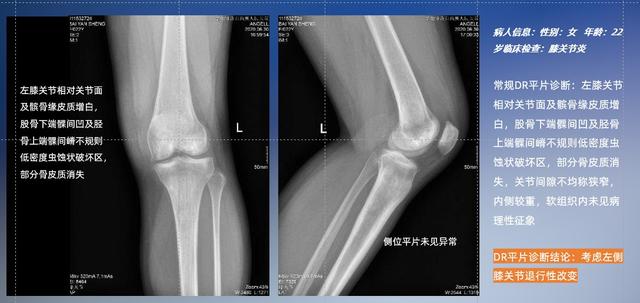

普通平片扫描与WR-3D扫描前后诊断结果对比

以膝关节疾病检查为例,膝关节在解剖学意义上是一种较为复杂的最大关节,由胫骨上端、股骨下端及髌骨组成。在股骨与胫骨的关节面之间存在两块半月板,分别处于内侧、外侧。膝关节的运动主要为伸、屈,在半屈位时可进行小幅度的旋外、旋内运动。随着现代人们体育生活以及肥胖的增加,膝关节疾病出现高发趋势,特别是关节磨损、膝关节炎与骨关节炎等关节退行性改变,长时间的内翻负荷会造成内侧关节软骨、骨性关节面的磨损。目前针对此类疾病的检查主要为平片下的负重位检查、CT检查以及MRI检查,相较于非负重位检查,负重位检查能更加真实反映膝关节结构中胫骨、股骨、髌骨实际对位关系和关节面的形态特征及关节间隙大小,对膝关节骨关节病诊断准确率高。

与此同时,数字化X线摄影技术相较于CTMRI来说,能快速获取真实、直观、满足临床需要的影像。DR的图像具有图像层次丰富、空间分辨力高、影像边缘锐利清晰、密度分辨力高级细微结构表现出色等特点,针对膝关节解剖结构数字化X线摄影技术应用价值很高,尤其是是对骨小梁与骨皮质的显示非常清楚。在负重位状态下,数字化X线三维摄影扫描与重建,能够更好的呈现受检者关节受力改变的状态。安健科技创新的WR-3D动态三维数字化X线摄影技术,通过数字化X线摄影完成三维扫描并重建三维影像信息,包括MPR多平面重建、MIP重建以及VR绘制。扫描时间短,剂量相较于CT设备大幅缩减,同时成本更低,在临床诊断以及医疗方案制定中具有极大的价值意义。相较于普通平片下的负重位扫描,负重位动态三维扫描摄影技术能够避免二维状态下的组织结构重叠、密度分辨率不足、组织解剖结构难以分辨等问题,WR-3D支持多角度的动态三维摄影观察,能全面的呈现被检查部位在多个角度下三维影像信息,极大的减少了二维负重位检查的漏诊率。